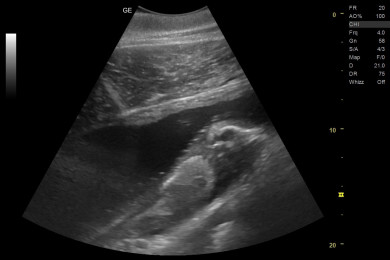

「テン」の妊娠については、2025年9月初旬に、体調管理のため定期的に行っている血液検査で兆候が示され、その後の超音波検査により胎仔の動きを確認しました。現在、妊娠6カ月を経過し、2026年7月上旬に出産を迎える予定です。なお、父親については、赤ちゃんの誕生後にDNA検査を行い特定する予定です。